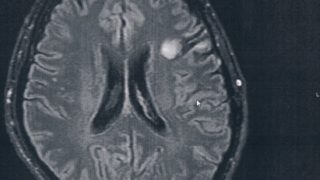

GLIOMA:手術後51ヶ月目の検査

半年ごとの定期検査のために久しぶりに病院に戻った。2014/6/23の覚醒手術から約51か月になる。MRI検査の結果、半年前と比べても変化は無いように見えるが、一年前やそれ以前の画像と比べると若干変化があるようにも見える。と先生が言う。今回...